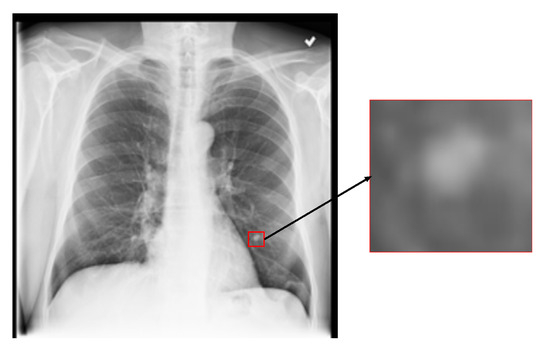

Commonly, CXR images are annotated with multiple disease categories, thereby framing the classification task as a multi-label problem. In this context, the predictive model is expected to concentrate on pathological features that are specifically relevant to each label. However, in practical scenarios, non-relevant visual information can interfere with the model’s ability to accurately identify disease-specific patterns. As shown in Figure 1, which presents a CXR image labeled with a “nodule”, the majority of the image comprises normal regions, while the lesion occupies only a small area highlighted by the red box. This limited spatial extent and the subtle nature of the abnormality pose a significant challenge for the model in isolating and learning discriminative features associated with the corresponding disease label.

Figure 1.

A CXR image with a lung nodule.